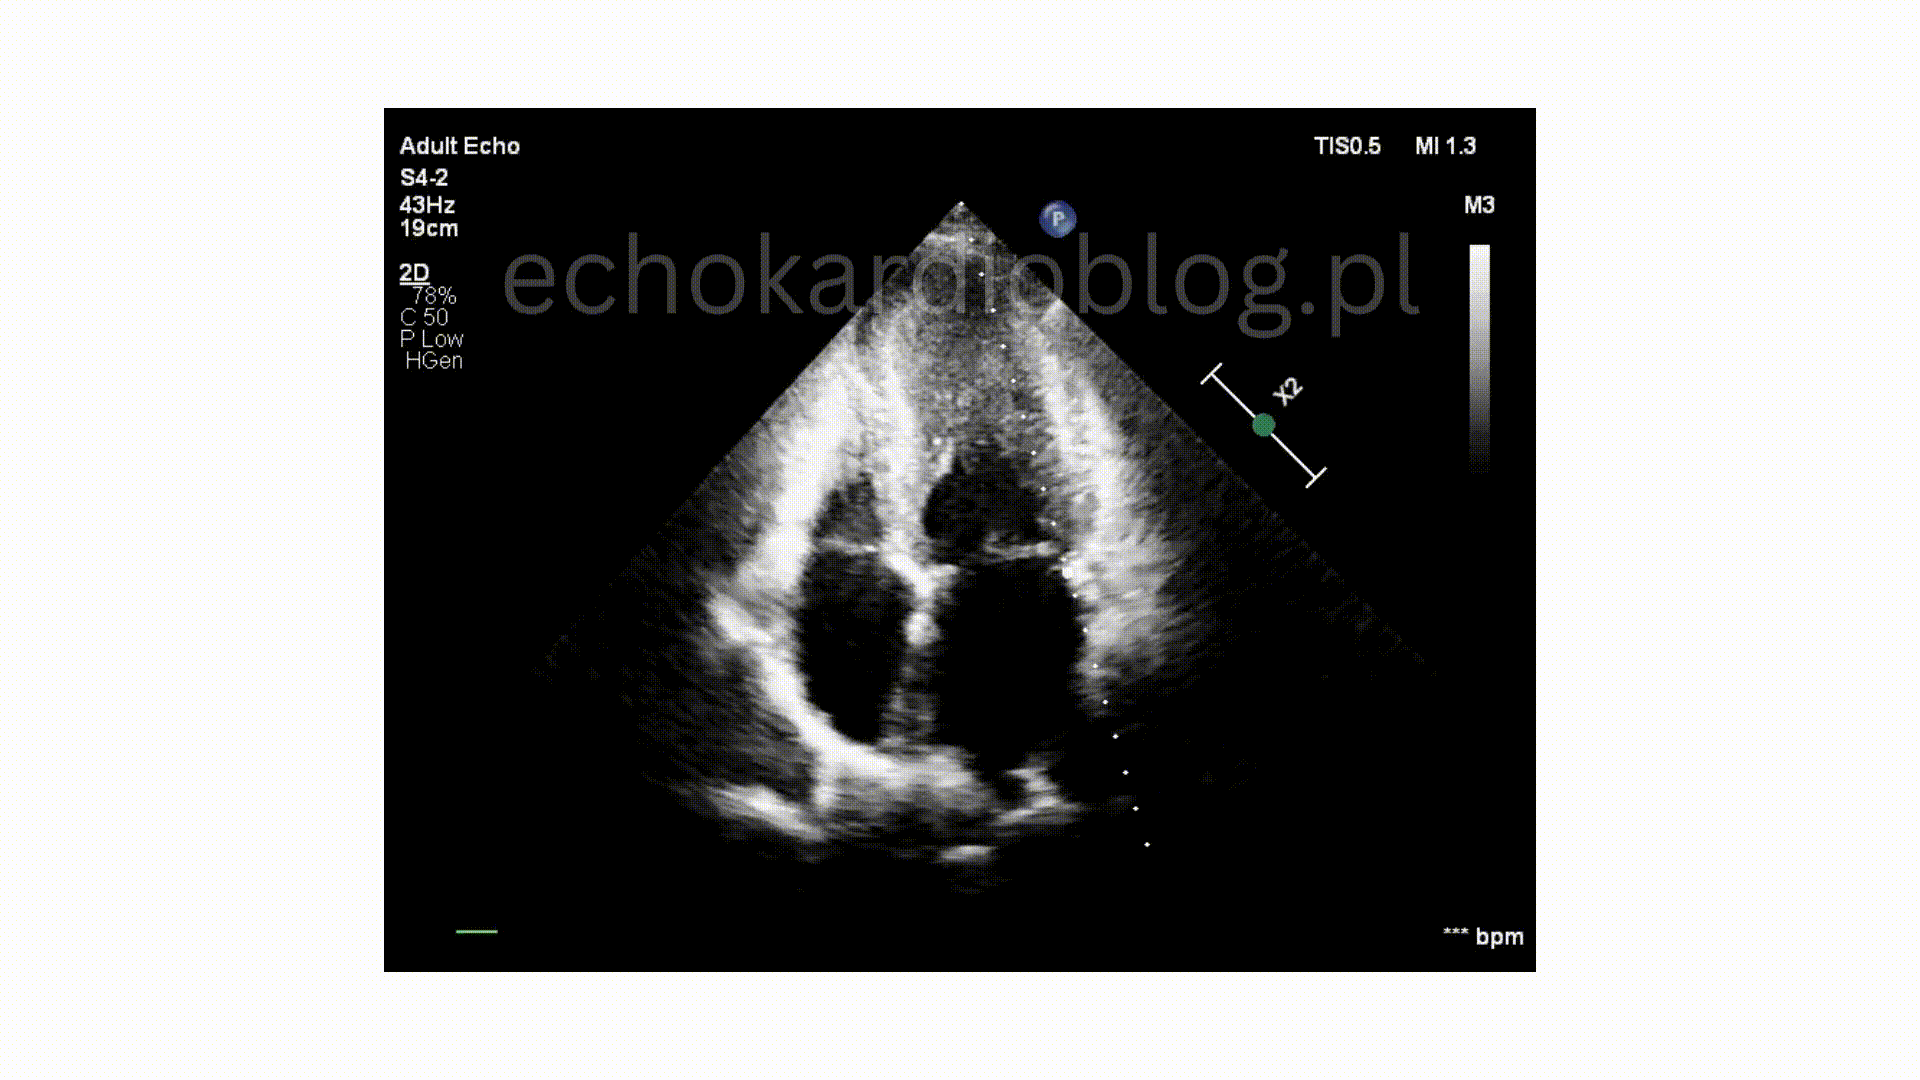

Pacjent , lat 66, przyjęty z podejrzeniem sepsy, w badaniu echokardiograficznym ujawniono duże, ruchome wegetacje na trzech zastawkach – mitralnej, trójdzielnej i płucnej . Wegetacje najlepiej widoczne były w projekcjach podmostkowych . Obraz jest dramatyczny: wysokie ryzyko powikłań zatorowych i przeciążenia prawego serca.

A 66-year-old patient admitted with suspected sepsis underwent echocardiography, revealing large, mobile vegetations on the mitral ,tricuspid and pulmonary valves .Vegetations were most clearly visualized in subcostal projections. The findings are dramatic, indicating a high risk of embolic complications and right heart overload.

w projekcji – podmostkowej 4 jamowej uwidoczniono wegetacje na zastawce trójdzielnej i mitralnej